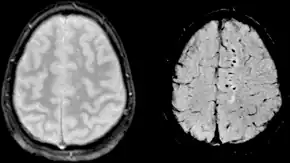

Clásicamente, la lesión traumática del cerebro se ha definido de acuerdo a criterios clínicos.[7][9] Las modernas técnicas de imagen como la resonancia magnética nuclear (RMN) muestran una sensibilidad cada vez mayor. Es posible que otros biomarcadores útiles se puedan desarrollar en el futuro.[2]

La lesión difusa se circunscribe básicamente a la lesión axonal difusa (LAD) y a algunos casos de tumefacción cerebral difusa (swelling). Una LAD es el corte de los axones en la sustancia blanca cerebral lo que causa la aparición déficits neurológicos no lateralizados como la encefalopatía. Las consecuencias de este tipo de lesión pueden tener un retraso de aparición de hasta 12 horas después del trauma. La LAD se produce por efecto de fuerzas inerciales que actúan sobre los axones durante unos 50 ms en sentido lineal o angular (por ejemplo, en colisiones frontales) lo que produce la desconexión y ruptura de los axones (axotomía primaria); no obstante la mayoría de los axones dañados (94%) son afectados por la axotomía diferida que consiste en un aumento a la permeabilidad de Ca++ en los nodos de Ranvier que causa la destrucción celular por excitotoxicidad. Ambas axotomías evolucionan desfavorablemente con cambios histopatológicos progresivos como son la formación precoz de bulbos de retracción axonal, acumulación de microglia y presencia de tractos de degeneración walleriana. La LAD puede ser identificada como hemorragias petequiales en la materia blanca (especialmente subcortical) en la TC y RM después de un TCE; sin embargo, los resultados pueden aparecer sutiles o ausentes en las imágenes. Los pacientes que padecen una LAD están subreactivos desde el momento en que se inflige el traumatismo porque la afectación axonal interrumpe las señales del sistema reticular activador ascendente y sus manifestaciones van desde una conmoción cerebral hasta la lesión axonal difusa grave.[8][5]

Usos de la Neuroimagen

La evaluación radiológica inicial es la misma que para cualquier paciente con trauma: radiografía (Rx) de tórax, de pelvis y de columna cervical.[13] El estudio de neuroimagen de elección en el TCE es TAC de cabeza sin contraste. A pesar de que el 15% de los pacientes con TBI tendrá una lesión aguda detectada por TAC sin contraste, sólo el 1% de estas anomalías requieren intervención neuroquirúrgica.[49][50] Aunque la resonancia magnética (MRI) es un 30% más sensible que la TAC para la detección de anomalías traumáticas después de un TCE, no hay evidencia que identifica mejor a los pacientes que requieren intervención neuroquirúrgica.[51]

- Resonancia magnética nuclear (RMN): Suele ser un poco más sensible que la TAC en detectar alteraciones pero tiene un costo demasiado elevado.[17]